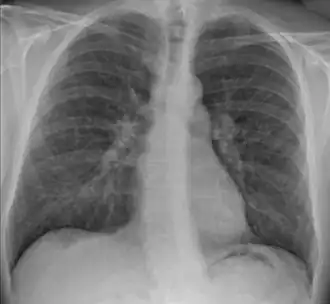

De ziekte wordt gekenmerkt door zogenaamde granulomen, kleine opeenhopingen van ontstekingscellen, en kent vaak een grillig verloop. Door vergrote lymfeklieren tussen de longen en soms verdichtingen in de long zelf is de ontsteking vaak zichtbaar op een röntgenfoto van de longen.

Voor de diagnose moet een arts de specifieke kenmerken vaststellen en andere oorzaken van de symptomen uitsluiten. De kenmerken zijn het beeld op de longfoto en de granulomateuze ontsteking. Tot de andere aandoeningen met vergelijkbare symptomen behoren tuberculose, longkanker en het kwaadaardig lymfoom (hodgkin en non-hodgkin).